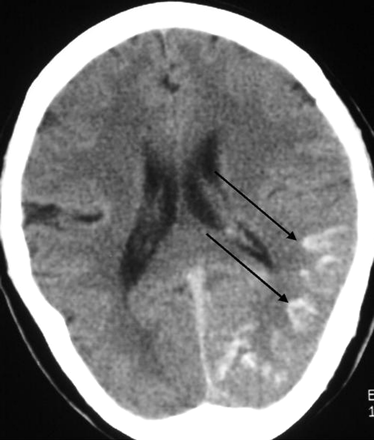

The imaging studies included noncontrast CT scan, 3D time-of-flight MR angiography (MRA) and MR imaging. CT demonstrated subcortical calcification, cerebral sulcus effacement, and a low attenuation area in the subcortical white matter on the left side (Fig 1). MR imaging (Fig 2) revealed multiple enhanced, punctate, and linear signal intensity voids, which indicates the presence of vessels over left cerebrum, and MRA showed multiple abnormal engorged vessels, which arose mainly from the external carotid artery. The left-side transverse sinus and sigmoid sinus were not identified on MR venography (Fig 2D). Digital subtraction angiography (DSA) revealed an AVF of the left transverse and sigmoid sinus (Fig 3) with main feeding vessels from both external carotid arteries. The main venous drainage was through the right transverse and sigmoid sinus, but there was retrograde flow into the straight sinus and superior sagittal sinus, which caused diffuse engorgement of the superifical cortical and the deep intramedullary veins. Occlusion of left transverse and sigmoid sinus was noted. Because of the retrograde flowing pattern of the dural sinus AVF and refluxing into cortical veins, the final diagnosis was type II a + b dural AVF.

Noncontrast CT scan, axial section of brain. Unilateral subcortical calcification (arrow) and mild adjacent sulcus effacement are seen. Relatively low attenuation appearance was noted in left cerebrum, which indicates the presence of venous ischemia or with infarction.

Diffuse engorgement of the superifical cortical and the deep intramedullary veins in our case are identified in the cerebral angiography and MR imaging. High pressure in these cortical and intramedullary veins results in local venous hypertension and impend local venous return. Venous ischemia, venous infarction, and even hemorrhage are likely to happen. The CT showed low attenuation areas in left posterior temporal and occipital lobe (Fig 1), suggestive of a nonhemorrhagic venous ischemia or infarct.